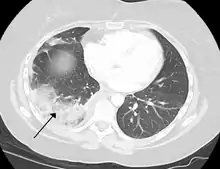

- Lung: Pulmonary infarction or lung infarction